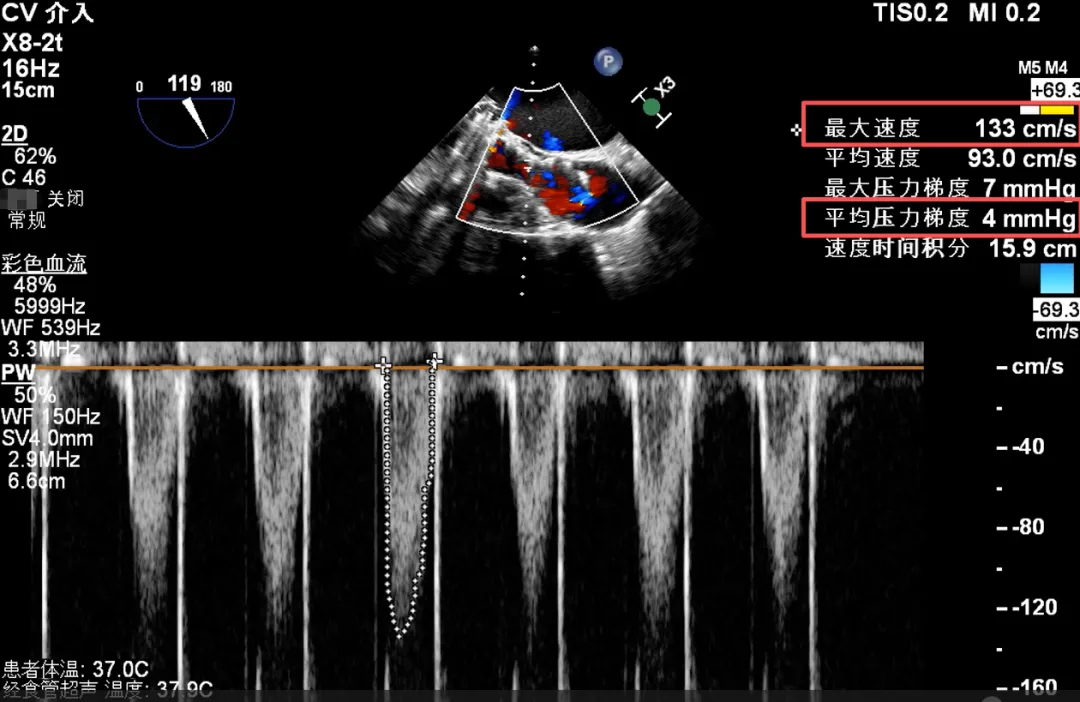

初冬的塞上大地,贺兰山脉覆着薄霜,黄河之水仍漾着温润波光,苍茫辽阔的西北风光里,藏着独有的坚韧与温情。这片孕育了西夏文化、承载着丝路底蕴的热土,自古便有着守望相助的人文情怀,而守护生命安康,更是这里医者们从未动摇的使命。在这片土地的医疗高地宁夏医科大学总医院,由刘旭东教授、李晓东教授、张玉京教授组成的心脏瓣膜专家团队,近日以一场高难度的创新手术,为心血管疾病患者点亮了新生希望 —— 成功完成全球首款预装干瓣 ProStyle A® 的全国首批临床植入。 此次手术的患者病情特殊,不仅主动脉瓣中度狭窄合并中 - 重度关闭不全、瓣叶增厚,还曾接受二尖瓣位机械瓣植入术,瓣膜锚定难度极大。团队历经多轮严谨评估,最终敲定采用 ProStyle A® 介入治疗方案,凭借精湛医术与周密预案精准完成瓣膜释放。这场手术的成功,标志着医院在结构性心脏病介入治疗领域迈入全生命周期管理新阶段,也成为国产创新器械与临床智慧深度融合的重要里程碑。 刘旭东教授 宁夏医科大学总医院 传统戊二醛保存的瓣膜,长期使用中易因组织钙化、柔韧性下降导致功能衰减。但 ProStyle A® 的优势在于两点:一是金仕生物的专利抗钙化技术,通过纳米级工艺去除组织内细胞碎片与磷脂,同时封闭游离醛基 —— 这相当于从源头阻断了引发瓣膜钙化的‘关键诱因’;二是干式存储技术,最大程度保留了心包组织原有的亲水亲油平衡,让瓣叶始终维持天然的曲柔性,确保长期开合功能稳定。对像此次手术这样的心功能受损患者来说,这种‘抗钙化 + 保柔韧’的双重设计,意味着瓣膜能更长时间地维持正常功能,减少二次干预的风险,真正实现‘一次植入,长期获益’,这正是全生命周期管理理念在器械选择上的核心体现。” 患者病史 主诉:反复胸闷气短2月余 术前超声提示:二尖搬位机械置换术后,功能未见明显异常,瓣周返流(轻-中度) 主动脉瓣狭窄(中度)并关闭不全(中-重度)VP:3.3mm/s,PG:45mmHg 三尖瓣返流(轻度) 左房显著增大左室明显增大主肺动脉增宽 左室收缩功能明显减低 术前CT 三叶瓣,瓣叶增厚轻度钙化,主动脉根部直径27.8mm,LVOT直径34.7mm。 双侧冠脉开口高度尚可,左右冠切线角度测量右冠瓣叶长于冠脉开口上缘到根部距离,瓦氏窦偏大。 左室腔扩大,EF较低,有一定循环崩溃风险,主动脉瓣环水平夹角52.7度,非横位心患者,主动脉弓宽度、角度可;二尖瓣机械瓣(横列式)置换术后AV-MV夹角130度,距离主动脉瓣虚拟瓣环6.67mm。 外周走行尚可,全主动脉基本无钙化,右股低分叉,血管内径可,血管内壁存在纤维增厚。右侧为主入路能够支持20F大鞘通过。 手术策略 右侧股动脉为主入路,预装ProStyle A® AV32主动脉瓣膜,使用20F大鞘,不预扩,建议最终理想释放位置0-瓣下2mm。 手术过程 在右股动脉穿刺建立通路后,将右冠送入冠脉保护,后顺利送入大鞘,经食道超声及血管造影确认路径稳定,将ProStyle A® AV32号瓣膜精准释放于目标位置(瓣下2mm),超声显示无瓣周漏,平均跨瓣压差4mmHg,心功能明显改善,患者生命体征平稳。 右冠保护 同时主动脉根部造影 定位 缓慢释放瓣膜 最终造影,位置形态良好,冠脉充盈良好 术后超声:显示瓣膜呈现较好的圆形,最大流速133cm/s,平均跨瓣压差显著降低至4mmHg,瓣周无反流。 ProStyle A®预装干瓣——助力临床最优化解决方案: 平衡径向支撑力:ProStyle A®瓣架网孔比例按照病例解剖结构的特殊设计,使瓣膜在狭窄最重的地方良好的撑开, 同时避免对瓣环及周边组织的过度压迫,有效降低传导阻滞风险。 精准释放:底部桶状设计更易迅速锚定,协同释放张力小,助力最终精准释放; 80%可回收设计:对于复杂解剖结构的患者,提供更充分的调整窗口,显著提升释放安全性与精准度并且80%可回收设计在释放过程中给予术者充分的容错空间。 预装干瓣 便捷顺安:金仕生物专利抗钙化技术运用纳米技术去除组织内的细胞碎片和磷脂,封闭游离醛基,从根本上阻断了瓣膜钙化的多项因素,显著提升了瓣膜的耐久性;同时,相比较传统戊二醛保存方式,干式存储最大限度的保留心包的亲水亲油平衡,还原组织天然曲柔性,进一步保障了瓣叶开合,保证长期耐久性。 专家简介 刘旭东 宁夏医科大学总医院(点击查看专家详细简历) 李晓东 宁夏医科大学总医院(点击查看专家详细简历) 张玉京 宁夏医科大学总医院(点击查看专家详细简历) · END ·